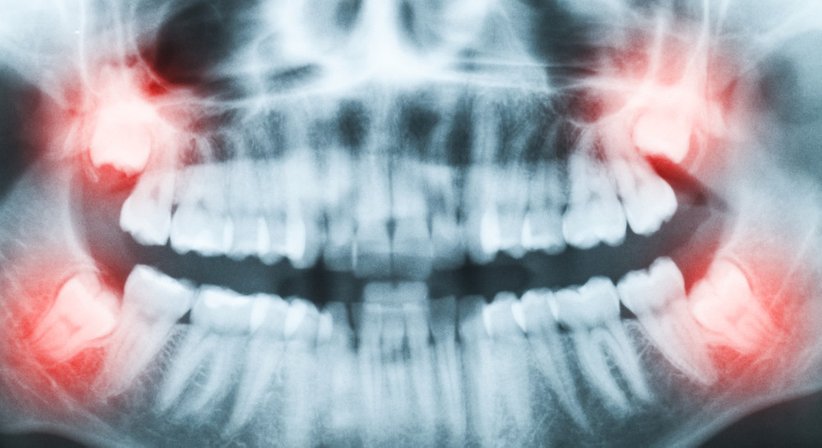

Auch kann es sein, dass der Zahnkeim falsch verlagert ist und der Weisheitszahn teilweise oder vollständig im Kieferknochen stecken bleibt, ohne die Kauebene (ganz) zu erreichen und die Schleimhaut zu durchbrechen. Mögliche Folgen und Komplikationen sind dann, je nach genauen Umständen, erschwerte Mundhygiene und erhöhtes Risiko für Karies, Zahnfleischentzündungen und Parodontitis, kariöse Schädigung der Weisheitszähne und benachbarten Zähne, schmerzhafte Abszesse, Zystenbildung, ausstrahlende Schmerzen im Gesichtsbereich u. a.

Die Entfernung von Weisheitszähnen zählt zu einem der am häufigsten durchgeführten Eingriffe im Bereich der Oralchirurgie. Zunächst erfolgt eine umfassende intraorale Untersuchung inkl. Übersichtsaufnahmen (digitale Volumentomographie, DVT), welche die Weisheitszähne mit ihrer genauen Position im Kiefer, Nähe zu anderen Strukturen, Wurzelform etc. zeigen, was es mir als Zahnarzt ermöglicht, etwaige Herausforderungen der Operation vorab gut einzuschätzen und die Behandlung vorausschauend zu planen.